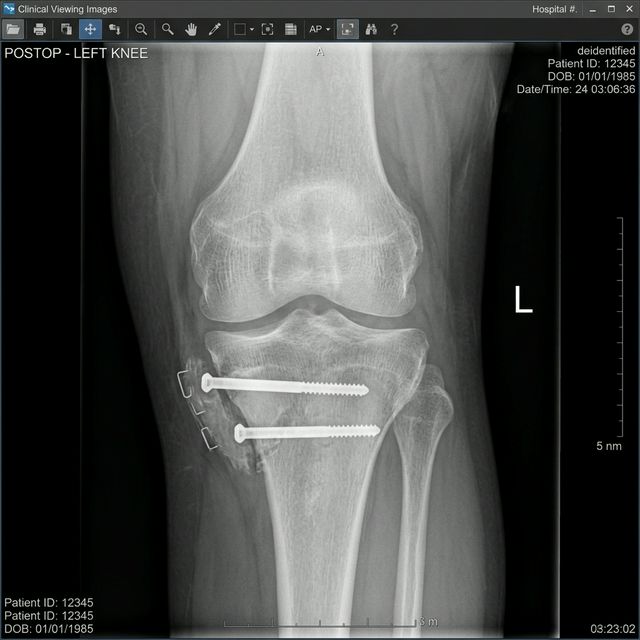

Clinical Results & Gallery

Tibial Tubercle Osteotomy (TTO) gallery 1

Internal Fixation

Securing the bone in its new position with two titanium compression screws for permanent stability.